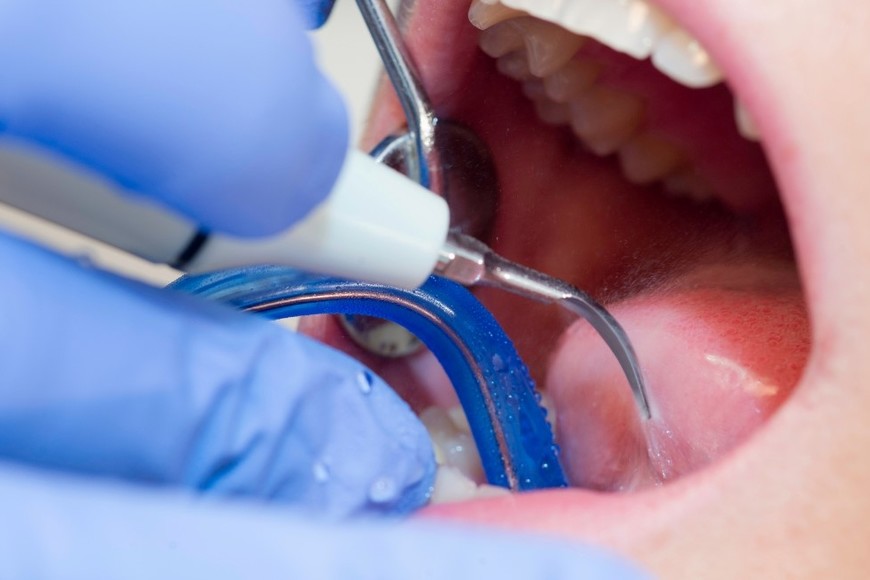

La tercera medida anunciada por la ANMAT, la Disposición 8705/2025, apunta a productos de uso odontológico que estaban siendo comercializados con datos falsos o certificados vencidos.

La investigación comenzó luego de que el Departamento de Control de Mercado recibiera una denuncia por la compra de un “Gel Acondicionador – Ácido Fosfórico 37%” a través de un sitio web.

El producto, identificado con el número de registro PM 1133-7, declaraba estar elaborado por MDT S.A. en un domicilio de la calle Heredia 665, en la Ciudad de Buenos Aires. Sin embargo, cuando los inspectores acudieron al lugar comprobaron que allí funciona una empresa de catering y no una planta elaboradora de insumos odontológicos.

Posteriormente, el organismo inspeccionó la sede de Company Dental, la firma vendedora. Allí encontró más de 80 jeringas prellenadas del mismo gel acondicionador en distintos lotes, así como unidades de amalgamas dentales de la marca Ventura, todas referidas a MDT S.A. o Macrodent S.A., y todas sin documentación que acreditara su procedencia.

La ANMAT consultó su base oficial y constató que:

las firmas MDT S.A. y Macrodent S.A. fueron habilitadas en el pasado,

sin embargo, actualmente no cuentan con certificado de Buenas Prácticas ni con registros vigentes,

los números de producto PM-1133-1 (amalgamas) y PM-1133-7 (gel acondicionador) están vencidos desde 2012 y 2016 respectivamente,

no existe ninguna actividad vigente de ambas empresas en el sistema Helena.

En consecuencia, el organismo concluyó que los materiales encontrados presentan riesgo para la salud, ya que no se puede garantizar su calidad, esterilidad, composición ni condiciones de elaboración.